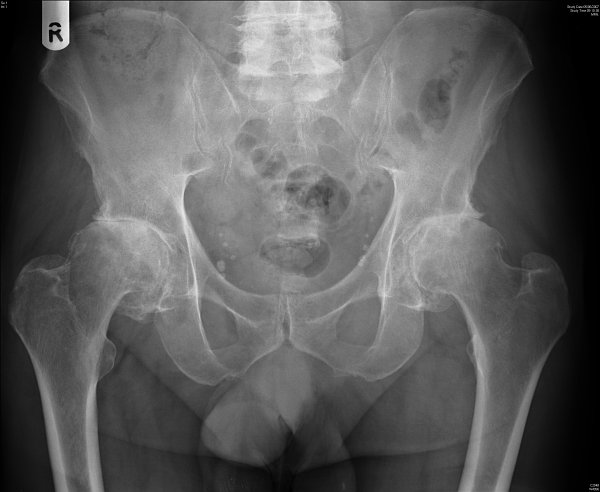

Osteoarthritis is a complex condition and researchers have found it difficult to identify its genes. Only two loci have been found so far in European populations – GDF5 and a signal from a region on chromosome 7.

The newly identified gene, MCF2L, is found on chromosome 13 and regulates a nerve growth factor (NGF). It has been reported that when people with osteoarthritis in the knee are treated with a humanized monoclonal antibody against NGF, they experience less pain and show improvement in their movement. This suggests that MCF2L is involved in the development of osteoarthritis and provides a new focus for future research.

“The discovery of this MCF2L variant suggests a possible genetic link to the finding that regulating NGF is important in knee osteoarthritis, and is supported by the fact that the variant is more strongly associated with knee osteoarthritis than hip osteoarthritis in the study. We hope the identification of this variant will lead to further insights into the biological processes at work and offer potential treatment targets.”